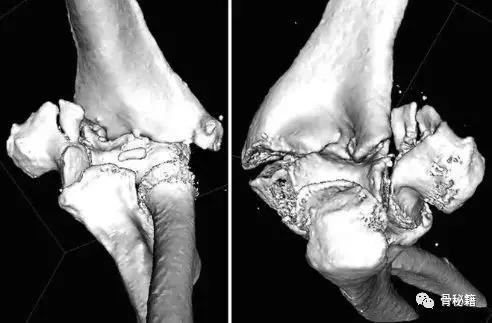

详细的术前评估

X线、CT、神经、等等

充分的的骨折显露手术入路(略)